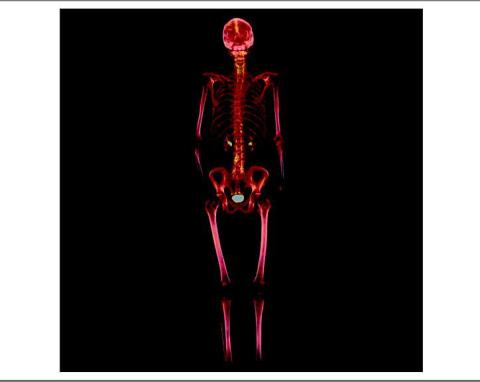

De første patienter er nu undersøgt på Rigshospitalet i PET & Cyklotronenheden, Klinik for Klinisk Fysiologi og Nuklearmedicin. Undersøgelsen er mere sensitiv end en almindelig knogleskintigrafi. Billedet viser en helkropsskanning af en patient med prostatacancer, hos hvem der er mistanke om knoglemetastaser. I lumbalcolumna og os sacrum ses der diskrete forandringer, der ikke er malignitetssuspekte.